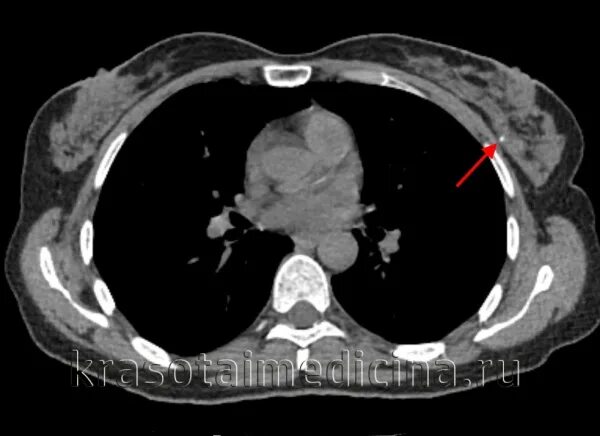

Причина образования кальцинатов